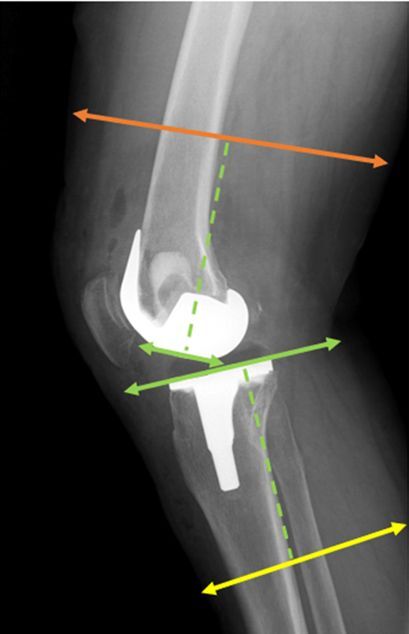

Fig. 2

Lateral view of lower limb measurement areas. The green dashed line marks a distance of 10 cm from the intercondylar line and the tibial plateau, marking the femoral and lower leg measurement regions indicated by the orange and yellow lines, respectively.